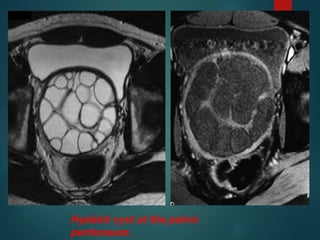

Hydatid cyst at the pelvic

peritoneum.

Hydatid cyst atthe pelvic peritoneum.